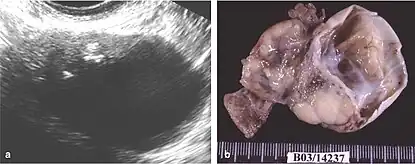

The difficulty in screening for SCC revolves around the creation of effective strategies with a positive predictive value. The timing aspect is crucial due to the lack of a specific timeframe for the onset of invasive disease or the interval stage between stage I and stage III carcinomas.[17] Ultrasound screening provides a detailed view of the ovaries, identifying morphologic changes as potential signs of malignancy. Key diagnostic factors include the presence of abnormalities, ovarian size, blood flow, and abdominal/pelvic fluid. The persistence of abnormalities after four to six weeks may decrease the occurrence of false positives. Screening protocols, often based on morphologic indices, utilize transvaginal ultrasound findings like cyst wall structure, septation, papillary projections, echogenicity, and ovarian volume to effectively detect malignancy.[17]

Although magnetic resonance (MRI) scans are not commonly employed for ovarian cancer detection, the majority of ultrasound-detected ovarian masses are usually benign. The combined approach of ultrasound with Doppler, along with the selective use of contrast-enhanced MRI, proves to be an efficient diagnostic method for identifying benign adnexal masses with distinctive features, including functional masses, dermoid, endometrioma, fibroma, pedunculated fibroid, hydrosalpinx, and peritoneal inclusion cysts.[19] This integrated diagnostic strategy is effective in preventing unnecessary surgical intervention. Additionally, the use of MRI contributes to a decrease in false-positive diagnoses, ultimately reducing the overall number of unnecessary surgical procedures related to ovarian masses.